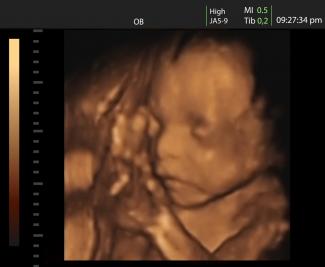

Podľa Reuters „boli plody, zjavne z druhého trimestra, ponorené v tekutine, ktorá obsahovala tkanivo ľudského mozgu.“

Významný pro-life advokát sa vyjadril, že „pozostatky nenarodených bábätiek naznačujú, že sa zrejme narodili živé počas neodborne vykonaného potratu.“

„Telíčka týchto bábätiek sú očividne prakticky neporušené. Ak sa tu ocitli po potrate, je vysoká pravdepodobnosť, že bábätká sa v skutočnosti narodili živé a zabili ich alebo nechali zomrieť až predtým, ako ich mali predať po častiach“. A na vysvetlenie dodáva: „V neskorých štádiach tehotenstva, ako boli aj tieto, to robia preto takto, lebo chemikália, ktorá sa používa na zabitie dieťaťa v maternici ešte pred vyvolaním pôrodu, by mohla poškodiť orgány a znemožniť tak ich použitie na experimenty.“